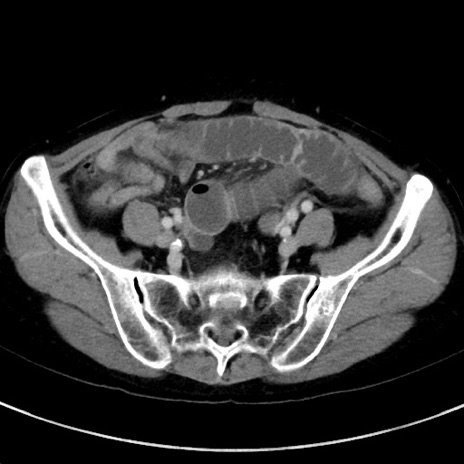

症例23(横断像)

【症例】70歳代女性

【主訴】下腹部痛・嘔吐

【現病歴】2日前より腹痛あり。昨日嘔吐あり。症状改善しないため来院。

【既往歴】胃GISTに対して胃部分切除後。

【身体所見】BT 37.1℃、BP 128/77mmHg、腹部:平坦・軟、下腹部に圧痛あり。

【データ】WBC 10200、CRP 0.31